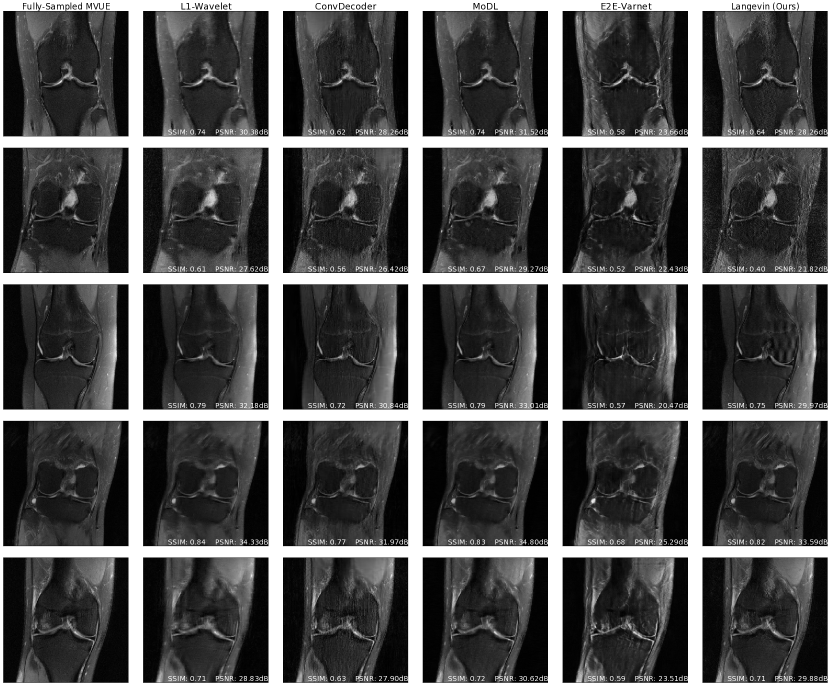

Refer to caption

Figure 3: Comparative reconstructions of a 2D abdominal scan with uniform random under-sampling in the horizontal direction at R=4𝑅4R=4. None of the methods were trained to reconstruct abdomen MRI. Our method uses a score-based generative model trained on brain images (as explained) and obtains good reconstructions. The red arrows indicate missing details or artifacts in the kidney structure.

Figures 2c & 5c show PSNR and SSIM scores obtained on reconstructed abdominal scans obtained from [1] at different acceleration factors. This represents both an anatomy and sampling pattern shift, and it can be seen that our method, MoDL, and the 1subscript1\ell_{1}-Wavelet algorithm retain their competitive advantage, while the ConvDecoder and E2E-VarNet suffer severe performance losses. Figure 3 further shows a qualitative comparison of a reconstructed abdominal scan at R=4𝑅4R=4, with highlighted artifacts. Appendix E shows another abdomen scan.